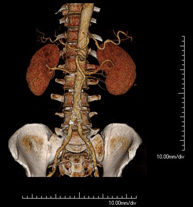

- Aortoiliac CT angiography

A non-invasive diagnostic test that involves examining the iliac arteries and abdominal aorta, obtaining high-definition anatomical images using CT (computed tomography) equipment and iodinated contrast dye. With the aid of workstations specialised for arterial studies, the image quality supports 2D and 3D reconstructions. This test is particularly recommended as a pre-surgical study (vascular map) prior to percutaneous or surgical interventions on the abdominal aorta, as a complementary study in patients with lower limb ischaemia, etc.